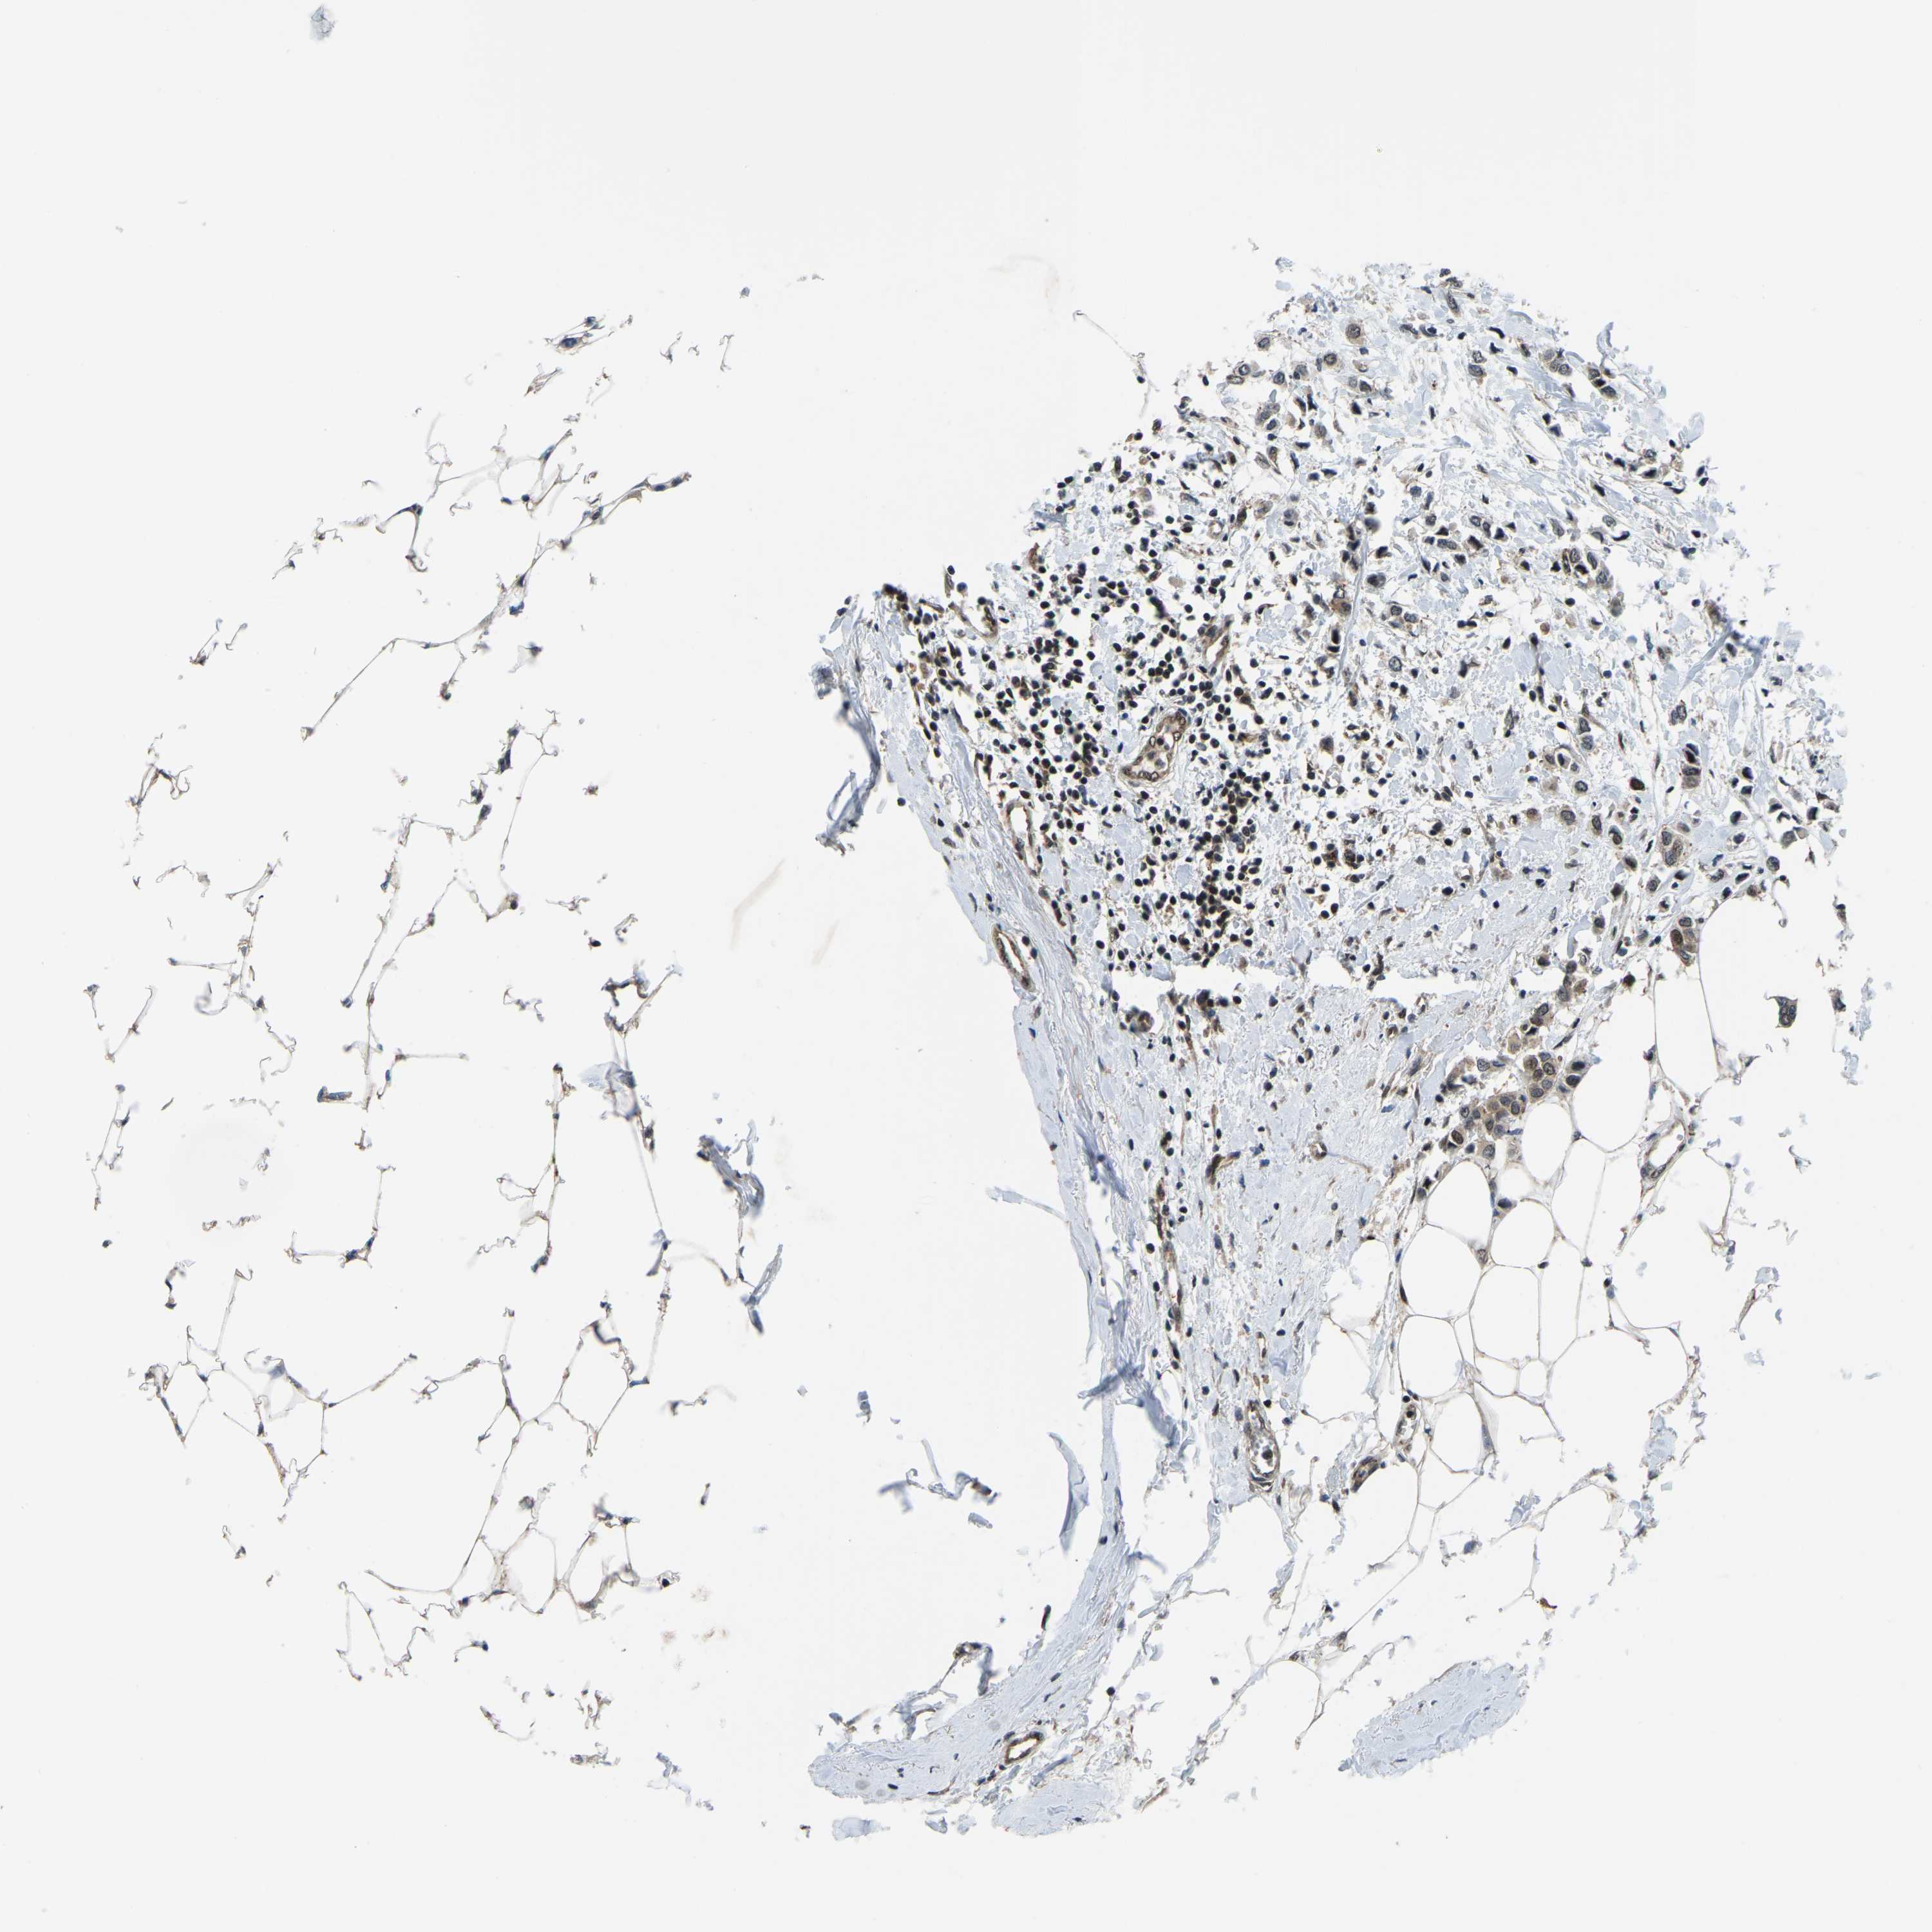

CANCER BREAST CANCER Show tissue menu

BRCA TCGA BRCA VALIDATION PROTEIN EXPRESSION